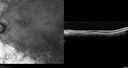

82 year old man with a sister with RP and no other family members. He has trouble with night vision. VA 20/25 OD, 20/32 OS. Note the symmetry in the FAF images typical for a dystrophy. The photos show bone spicules, arteriol attenuation and optic nerve pallor

Retinitis Pigmentosa - Autosomal Recessive - 82 year old man with Good Vision479 viewsVA 20/25, 20/32 - Bone spicules in periphery - FAF is very symmetric     (0 votes)